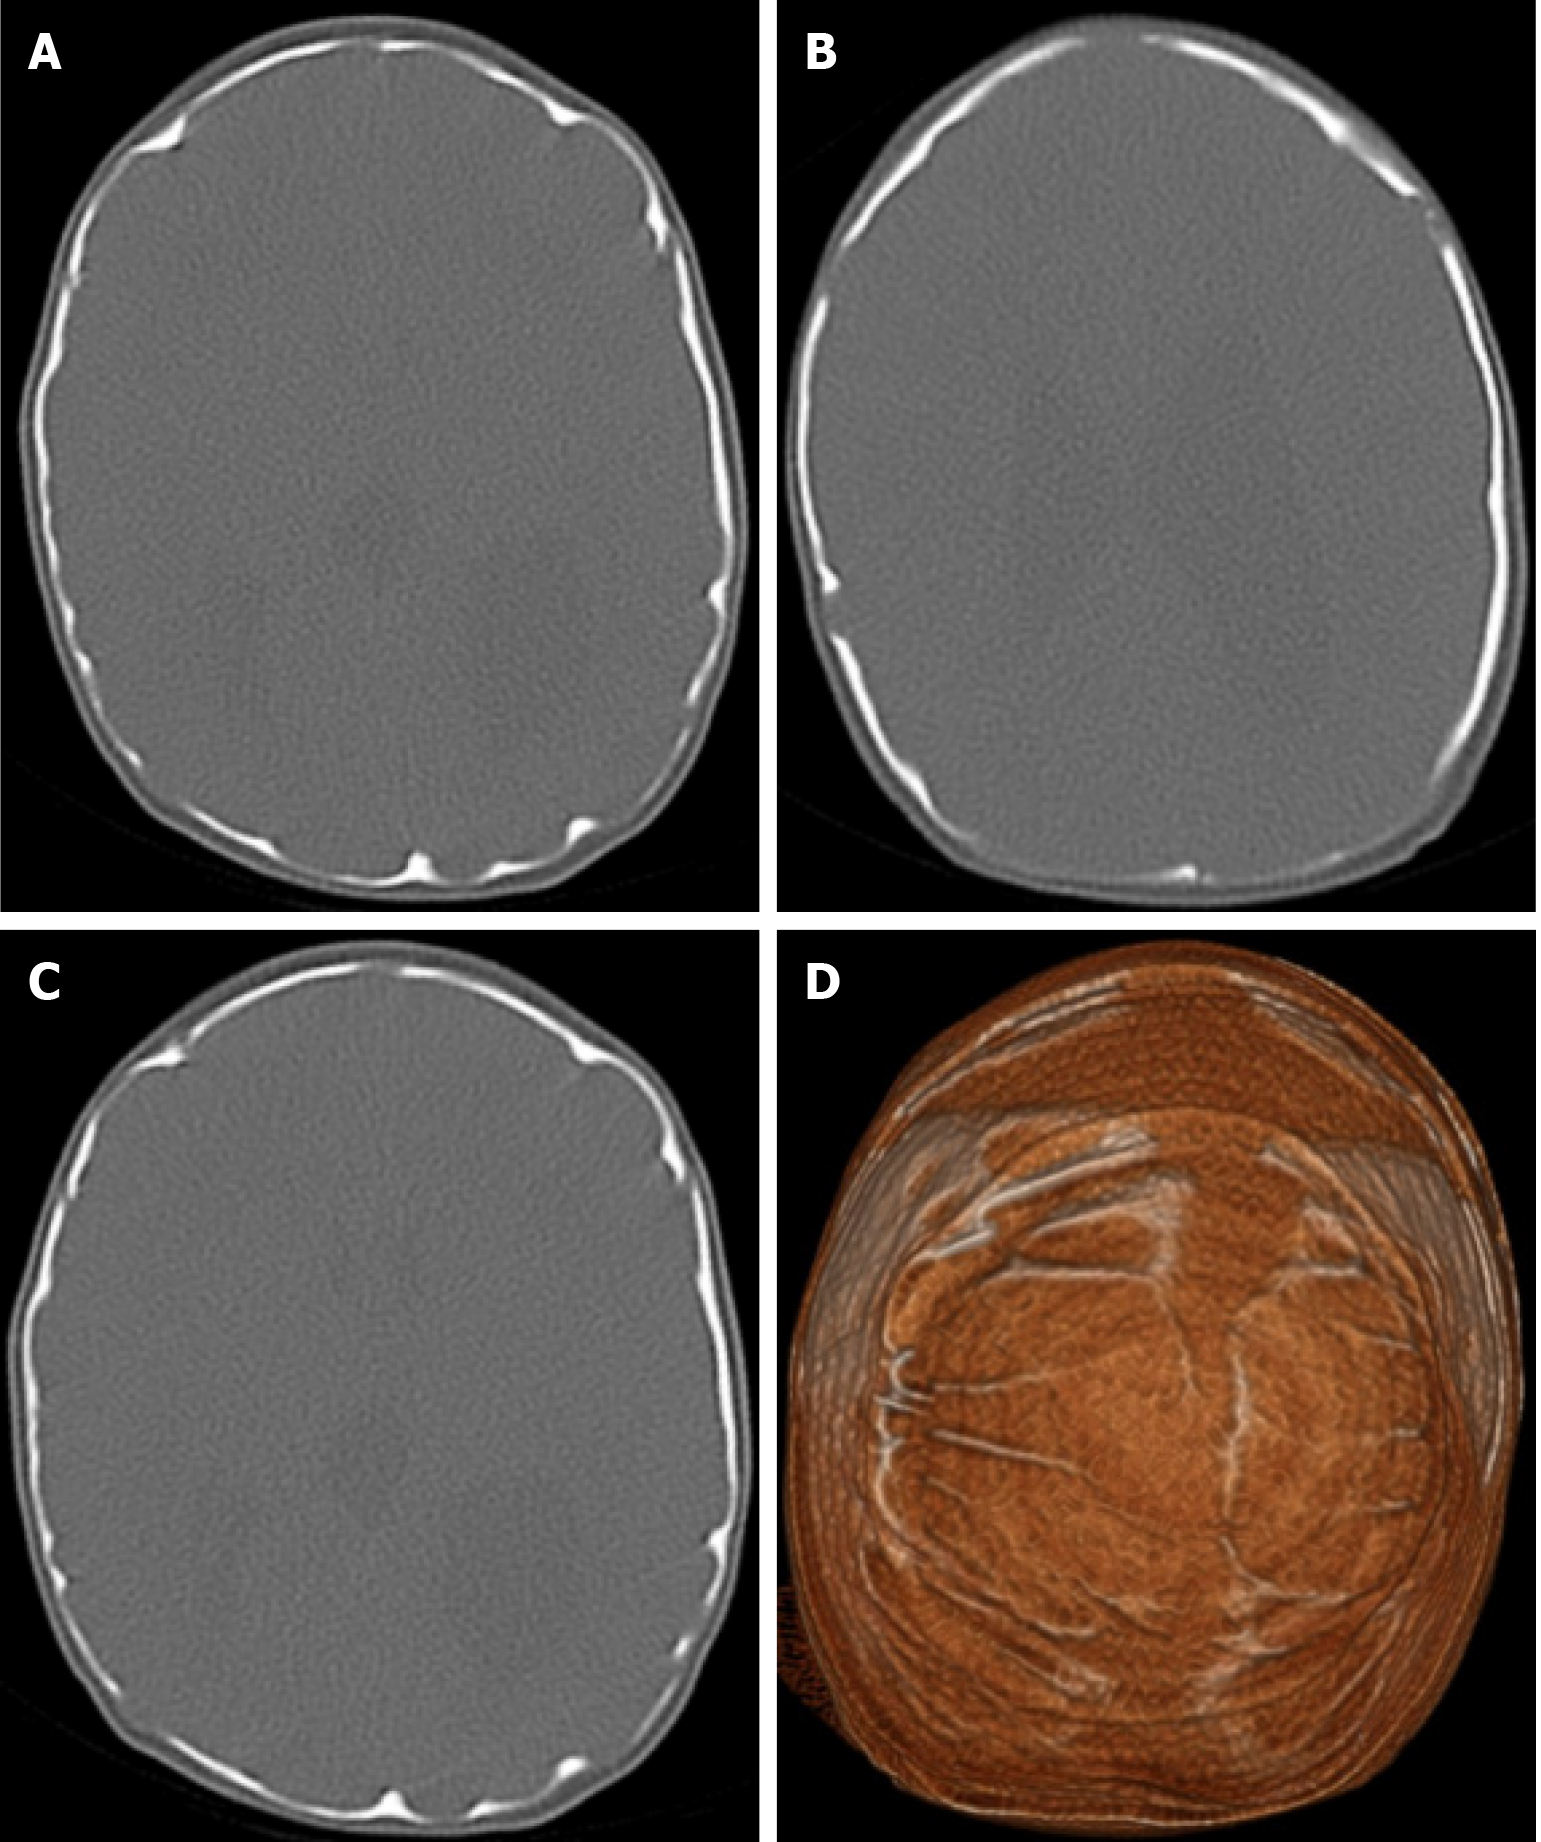

The beaten copper skull shows prominent convolutional markings on several bones of the skull. These convolutional markings normally appear between the ages of 2-3 and 5-7 years, which are periods of rapid brain growth. The occurrence of convolutional markings in children younger than 18 months should suggest a cause leading to increased intracranial pressure due to processes such as obstructive hydrocephalus, craniosynostosis or intracranial masses. Beaten copper skull pattern develops because of pressure applied to the soft skull by the growing brain. The beaten copper skull is usually confined to the posterior part of the inner table of the skull, but this appearance can affect the entire skull. Plain radiography of the skull can be an important diagnostic tool to detect increased intracranial pressure. In children, CT and three-dimensional reconstructions are best used to evaluate the convolutional markings (Figure 5) and cerebral ridges for surgical planning[23].